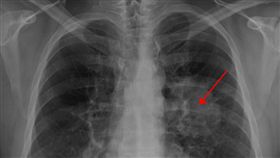

少數肺癌患者 「初期連咳嗽都沒有」

衛福部發布107年國人死因統計,致死率最高的,毫無疑...

初期肺癌拖成末期 醫曝這件事害了他

生病不能拖延治療,尤其是癌症。如果健康檢查早已發現異...

長期咳嗽、胸悶 27歲男驚罹肺腺癌

民眾有長期咳嗽、胸悶的困擾嗎?千萬別輕忽!新竹一名2...